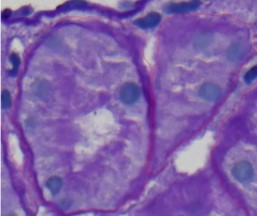

The AI model’s annotations in the provided histological image appear to be of high quality. The red lines accurately trace the boundaries of cellular structures, indicating good alignment with natural edges. The annotations cover most visible structures, suggesting completeness. Consistency is maintained throughout the image, with similar structures being outlined similarly. The clarity is upheld by using thin lines that do not obscure important details, and the annotations follow the contours of the structures specifically, reflecting the model’s capability to recognize fine details. Overall, the annotations are accurate, complete, consistent, clear, and specific.

you will see in thus two image the high quality of annotations by AI, in this model we increase the number of epochs and we change the number of batch size 2 to 1.

quality of but in some where you will see that the separations between two object it’s no complete as you can see in the image in bellow but also they annotated the objet really good they exclude the nuclei and annotated all mainframe and sharing Mein brane between tubuli and peri tubuli capilari (PTC).

This image appears to be a microscopic view of a tissue sample, likely stained using a method such as Hematoxylin and Eosin (H&E) to highlight cellular structures. The deep purple areas represent cell nuclei, while the lighter purple areas are the cytoplasm and other tissue components. The red lines overlaying the image indicate that an AI tool has been used to annotate specific structures within the tissue. These annotations typically highlight important regions of interest, such as cell boundaries or areas indicative of pathological changes. The precision of the annotations suggests that the AI model is proficient in recognizing and delineating complex biological structures, which is crucial for tasks like histopathological analysis. The AI’s ability to accurately annotate these features can assist pathologists in diagnosing diseases, ensuring that subtle morphological changes are not overlooked. This combination of AI and histology exemplifies how technology can augment traditional medical practices, leading to more efficient and accurate diagnostics.

As you can see in This image is a microscopic view of a tissue sample stained with Hematoxylin and Eosin (H&E), highlighting cell nuclei in deep purple and cytoplasm in lighter purple. The red lines are AI-generated annotations, accurately outlining cell boundaries and key structures. The precision of these annotations showcases the AI’s capability in histopathological analysis, aiding in disease diagnosis by providing reliable and consistent identification of cellular components. This integration of AI enhances the efficiency and accuracy of medical diagnostics.